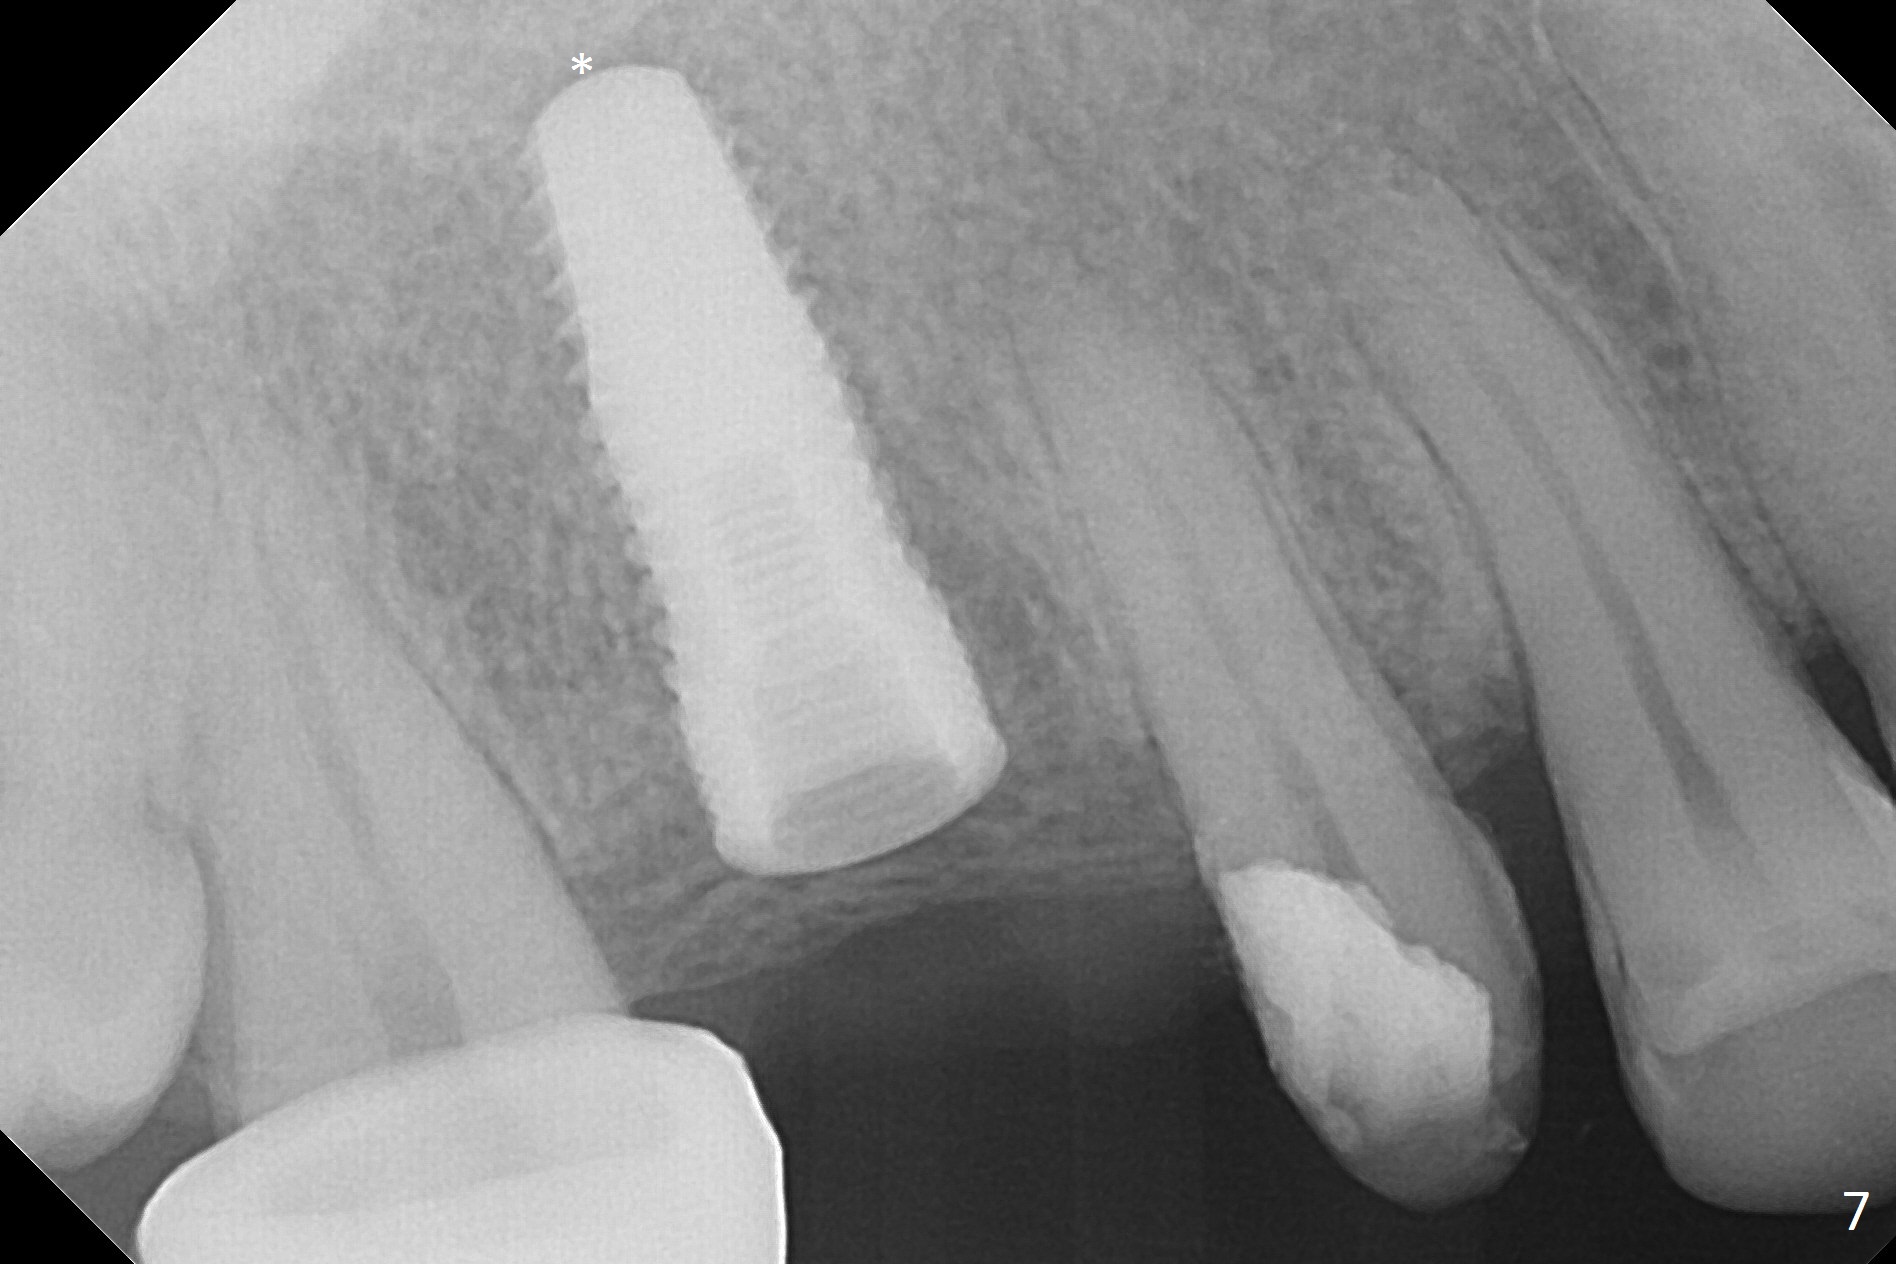

When the bridge is partially removed, the tooth #4 is found to have extensive caries. IRM is placed following carious removal (Fig.1). Magic Split testing shows that the bone density is high (flapless). Osteotomy is initiated by 1.6 mm drill, but the handle of the drill needs to shift mesial (Fig.1 red arrow). When the latter is done, the whole drill (2 mm) needs to move distal (Fig.2 double red arrows). When a 4.5x14 mm drill finishes the osteotomy, it is in the middle of the edentulous space (Fig.3). After use of 5 mm tap, a 5.3x14 mm implant cannot reach the depth (Fig.4,5). Following increase in osteotomy depth from 16 to 18 mm (gingival margin) until 5 mm drill in diameter, the implant placement level is more ideal (Fig.6,7, slightly subcrestal) with insertion torque maintaining at >55 Ncm. The sinus floor (Fig.4 arrowheads) may be penetrated when the osteotomy depth increases (Fig.7 *), but the sinus membrane remains intact.